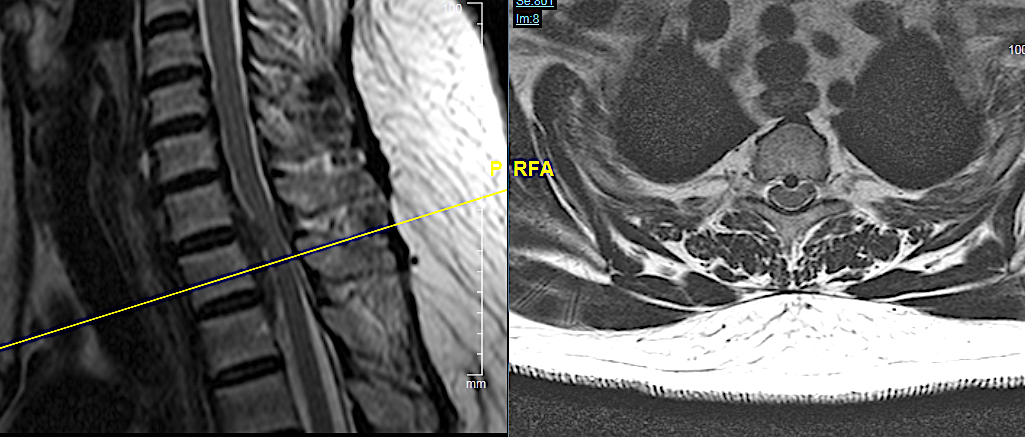

CASO CLÍNICO 1: HERNIA DISCAL TH1-TH2 MIGRADA CAUDALMENTE (con engrosamiento calcificado de LVCP hasta Th2-Th3).

Paciente de 58 años con dolor radicular refractario de >6 meses en MSD, acompañada de pérdida de fuerza en la musculatura intrínseca y atrofia muscular. EMG presenta afectación severa crónica en raíces C7-C8-Th1 derechas.

Obsérvese HDTh1-Th2 con migración caudal retrosomática (Th2)

Obsérvese el engrosamiento de LVCP de aspecto calcificado

El compromiso anterior del canal (a pesar de la radiculopatía severa en MSD) me obliga a plantearme un abordaje anterior con posibilidad de ampliar el campo a través de una esternotomía.